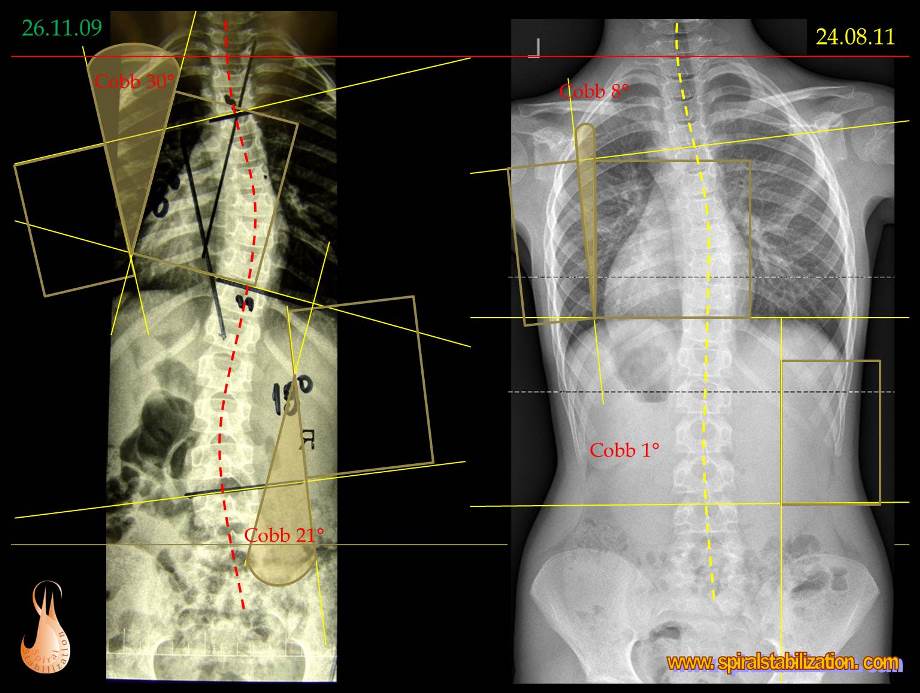

Veľkosť deformity sa hodnotí vo všetkých troch rovinách. Metódou podľa Cobba možno odčítať uhlovej zakrivenie v predozadnej projekcii (AP = Antero-posterior) a v bočnej projekcii (sagitálnej rovine). Modernými zobrazovacími metódami možno navyše v osovom reze trupu (v transversálnej rovine) odčítať rotáciu chrbtice.